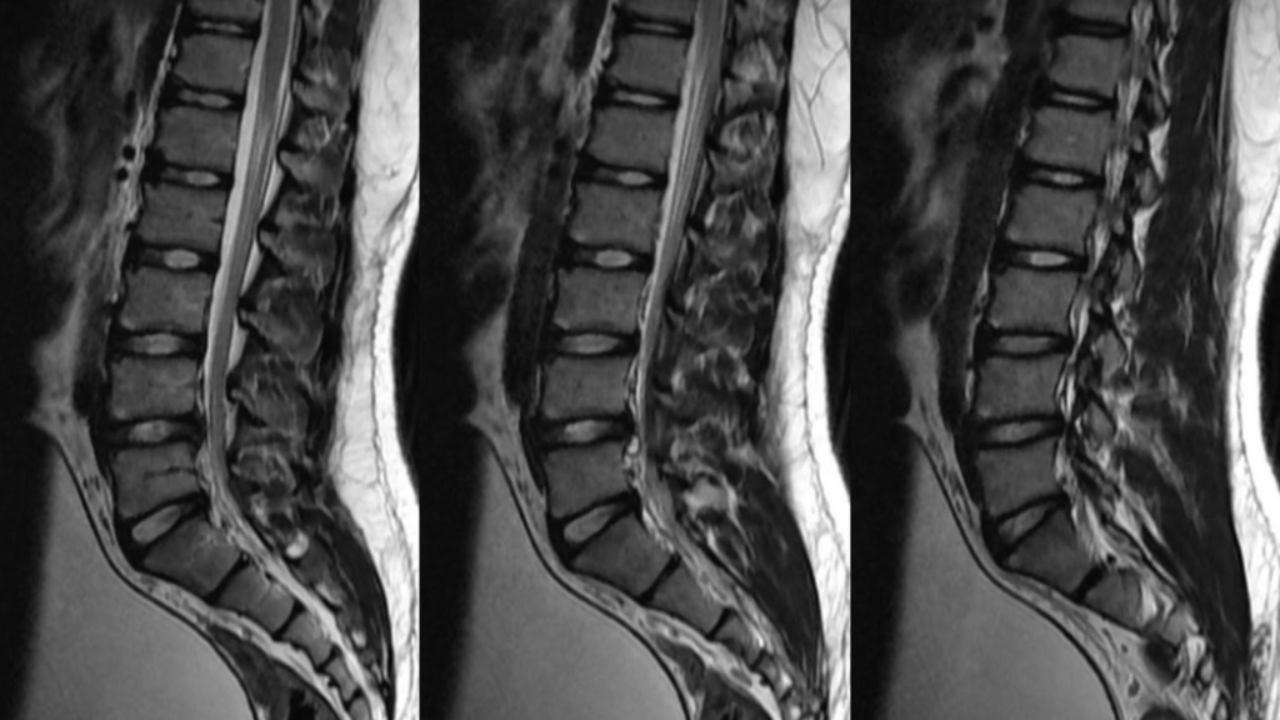

And these harmful misleading nocebic effects are not just seen with posters and infographics in healthcare, they are also, unfortunately, a very common side effect of many medical images used in healthcare such as Xrays, CT scans, MRI's and Ultrasounds.

However, where medical imaging is failing many people is when it is being used inappropriately and incorrectly to explain why some things hurt in some people. This is due to many clinicians and patients thinking that pain and disability can be explained simply when a structural irregularity is seen on a scan such as a bulging or herniated disc, a misshapen or degenerative joint, or a torn or inflamed tendon, this, unfortunately, is just not true.

There is growing evidence that many things seen on scans in those with non-traumatic pain are found very commonly in people with NO pain and NO disability. We are beginning to recognise and understand that what we thought was pathology and sources of pain and other symptoms may just be normal variations in normal anatomy or natural ageing process.

For example, Guermazi et al (2012) demonstrated that ALL the common pathologies are seen in knee scans such as meniscal lesions, synovitis, and articular cartilage damage are found just as much, if not more often in subjects WITHOUT pain as those with pain. Also, Brinjiki et al (2014) showed that there is a high prevalence of structural irregularities of the lumbar spine seen on MRIs of more than 3000 people aged between 20 to 80 years olds who again had NO pain, disability or any other issues.

And this is just some of the evidence in the shoulder joint alone, I could go on and on presenting study after study conducted on pain-free, fully able subjects that shows so-called pathology in all areas of the body such as the hip, knee, foot, elbow and of course the spine! This large body of evidence available proves that many things we see on scans in those with pain and other symptoms are also seen just as often, if not more in those without any pain or symptoms.

Things often labelled as pathology on scans are often just normal variations in anatomy or morphology, or just normal signs of age. It is not as simple as just seeing a worn-out, misshapen, or torn structure on a scan and assuming it is the source of someone's pain.

A nice comparison here is looking at a photo of a wedding where everyone is grouped around the happy couple. In this photo, everyone is smiling and looking happy, but you cant determine who actually is happy just by looking at the photo. This is the same as when looking at an MRI of someone's spine or shoulder, we may see things that look unhappy on the scan, but we can't actually tell if it is actually unhappy just by looking at the scan.